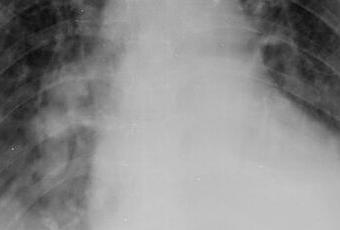

TÓRAX AP

LA PROYECCIÓN RADIOGRÁFICA OBTENIDA MUESTRA LOS SIGUIENTES HALLAZGOS:

Tejidos blandos simétricos, sin cambios en su densidad.

Silueta cardiomediastinica, con aumento del tamaño cardiaco.

Botón aórtico, con presencia de calcificaciones.

Tráquea, central.

Hilio pulmonar, sin evidencia alteraciones. A nivel parahiliar bilateral, con presencia de nódulos que mide de lado derecho 4 × 7 mm y de lado izquierdo 9 × 5 mm.

Ambos campos pulmonares, con presencia de patrón retículo nodular, así como áreas en vidrio esmerilado de predominio basal.

Recesos costofrénicos ocupados. Recesos cardiofrénicos aparentemente libres.

Estructuras óseas, sin evidencia de lesiones líticas, blásticas o perdida de la contigüidad.

impresión diagnostica:

EN EL PRESENTE ESTUDIO RADIOGRÁFICO, CON IMÁGENES SUGERENTES DE NEUMOPATÍA INTERSTICIAL AGUDA, ASÍ COMO APARENTE FOCOS NEUMÓNICOS BASALES BILATERAL Y CARDIOMEGALIA, ASÍ COMO LA PRESENCIA DE DERRAME PLEURAL BILATERAL.

A NIVEL PARAHILIAR BILATERAL, CON PRESENCIA DE NÓDULOS QUE PODRÍAN CORRESPONDER A GANGLIOS.

CORRELACIONAR CON DATOS CLÍNICOS Y ANTECEDENTES DE CONSIDERARSE NECESARIO POR MÉDICO TRATANTE, COMPLEMENTAR CON ESTUDIOS ADICIONALES O DE CONTROL, SEGÚN EVOLUCIÓN CLÍNICA DEL PACIENTE.